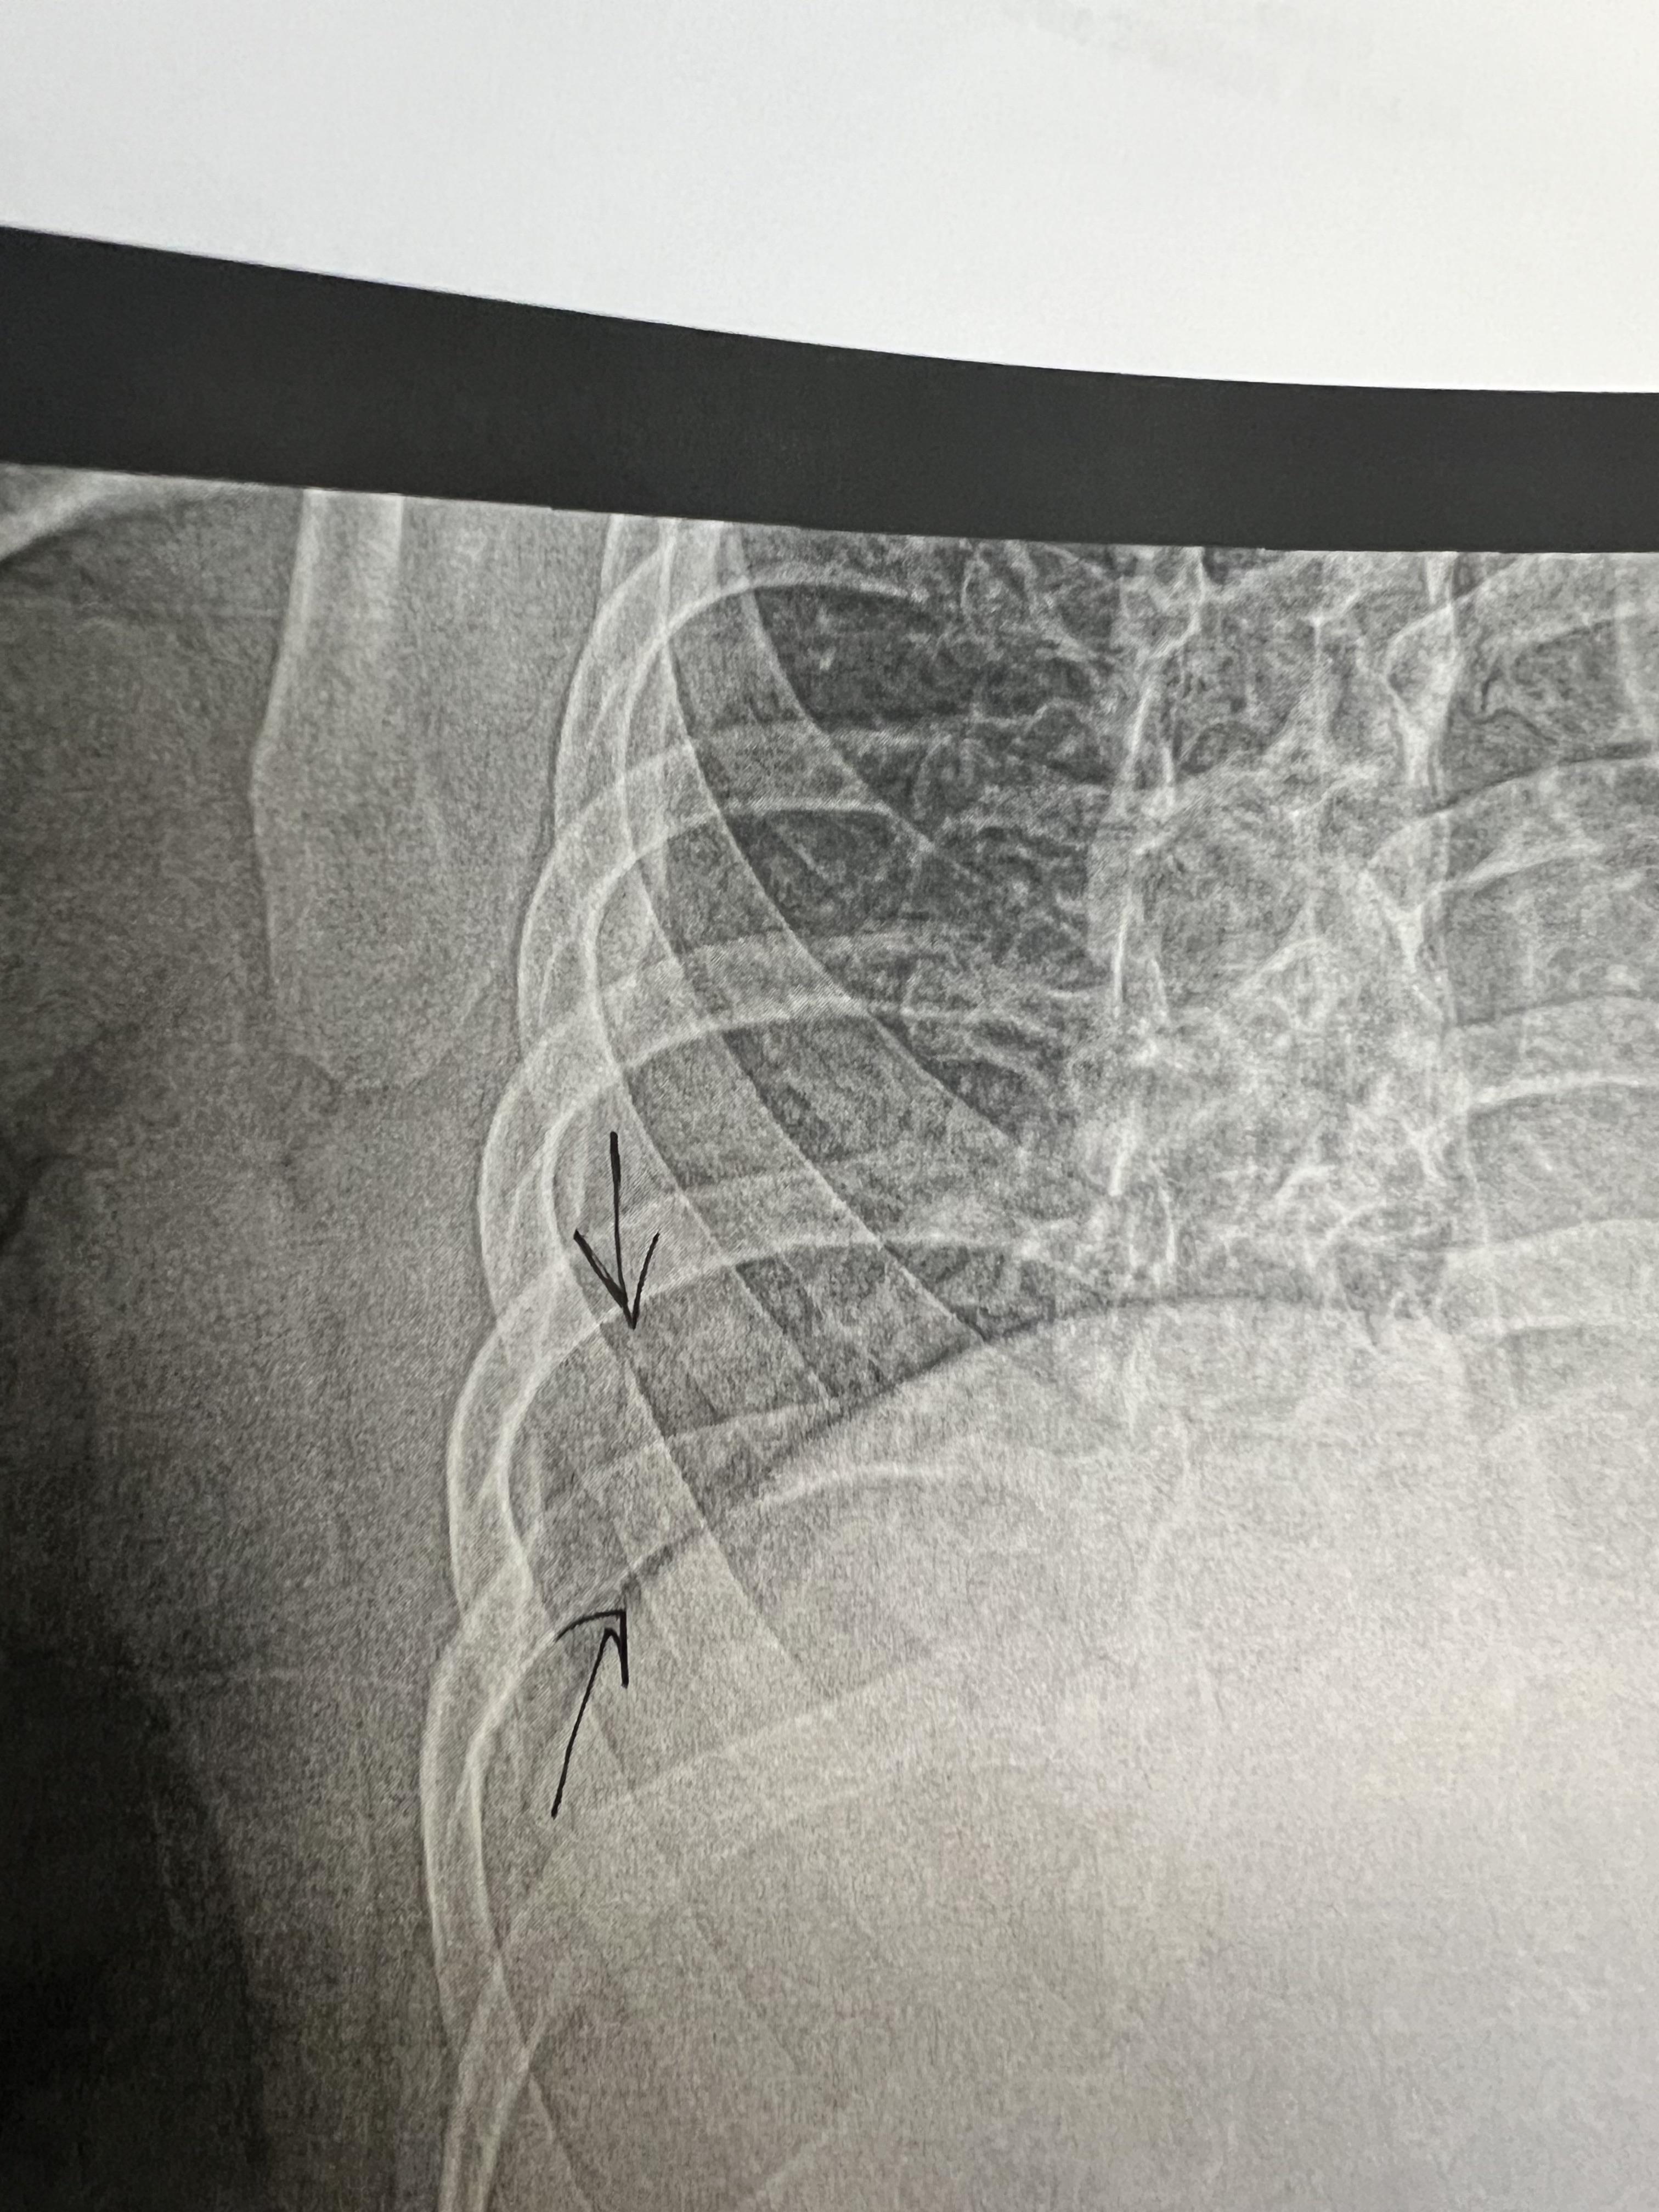

From www.reddit.com

Broken rib from a coughing fit r/Radiology Ribs Hurt From Coughing Too Much Injuries to the chest from a fall or hard hit. Acute costochondritis, also called chest wall pain syndrome, is a common cause of pain in the front of your chest near the breastbone (sternum). Exercises or sports with repetitive movements, twisting, lifting or stretching. Rib pain from coughing can be caused by persistent or violent coughing. If your rib pain. Ribs Hurt From Coughing Too Much.

I broke some ribs while coughing from pneumonia! r/Radiology Ribs Hurt From Coughing Too Much Rib pain following traumatic injury may be due to rib. If your rib pain is severe, unexplained, and accompanied by shortness of. Rib pain from coughing typically resolves with treatment within a few days or weeks. Muscle strains may occur with an injury or even coughing or bending. Ribs can also be bruised (bone bruise). Rib pain from coughing can. Ribs Hurt From Coughing Too Much.